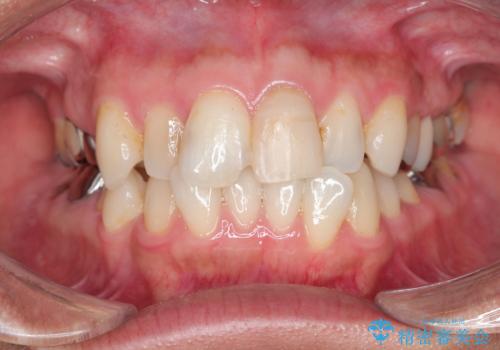

- 15.4万円(ジルコニアクラウン・仮歯・ファイバーコア)費用は治療当時の料金となります

周囲の歯と調和した審美的な仕上がりに満足いただくことができました。